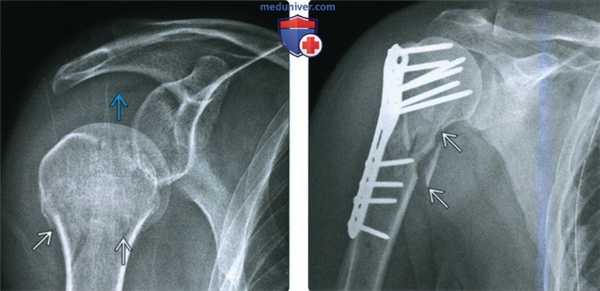

(Слева) На передне-задней рентгенограмме определяется перелом плечевой кости Ниера из одного сегмента. Имеется липогемартроз, указывающий на внутрисуставное поражение, и сниженный мышечный тонус, вызывающий легкий нижний подвывих.

(Справа) На передне-задней рентгенограмме можно видеть сопоставление, а также и закрывающую пластину и фиксацию шурупами при оскольчатом переломе хирургической шейки. Оперативная фиксация предупреждает неправильное срастание, которое часто приводит к хронической боли и слабости.